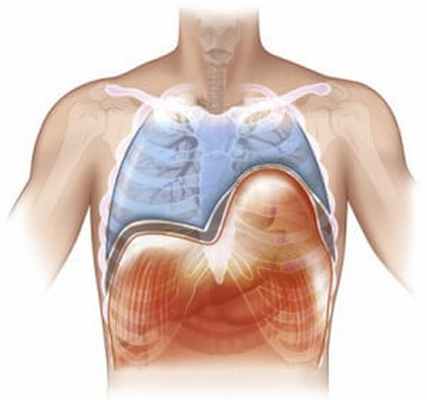

Диафрагма (diaphragma от греч. — перегородка), или грудобрюшная преграда — это куполообразная перегородка, которая разделяет грудную и брюшную полости. Выделяют центральную сухожильную и краевую мышечную части диафрагмы. Сокращаясь и расслабляясь диафрагма принимает участие в акте дыхания.

Релаксация диафрагмы – одностороннее стойкое высокое расположение диафрагмы, сохраняющей свою непрерывность и прикрепление в обычных местах.

В основе заболевания — повреждение диафрагмального нерва, при котором диафрагма расслабляется и не сокращается (т.е. наступает её релаксация). Так как в брюшной полости положительное давление, а в грудной клетке в большей части отрицательное, то органы брюшной полости давят на релаксированный купол диафрагмы. Таким образом, купол диафрагмы поднимается выше обычного, сдавливая собой соответствующее легкое. Часто заболевание так и называют — релаксация купола диафрагмы.